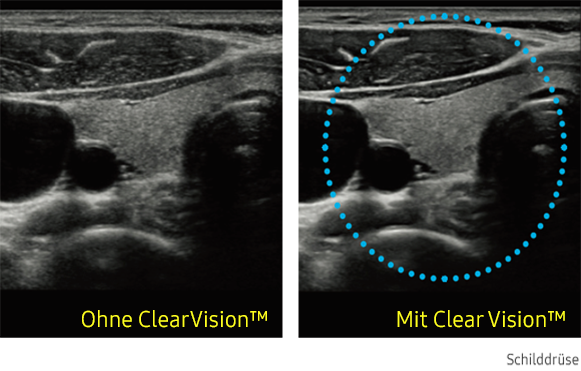

ClearVision

Der Rauschunterdrückungsfilter verbessert die Kantendarstellung und schafft schärfere 2D-Bilder für eine optimierte Diagnoseleistung. Die Integration dieser spezialisierten Samsung-Technologie führt zu einer bemerkenswerten Verbesserung der Bildqualität. Darüber hinaus bietet ClearVision anwendungsspezifische Optimierungsmöglichkeiten und eine erweiterte zeitliche Auflösung im Live-Scan-Modus.

Ultraschallbild Schilddrüse links ohne ClearVision und rechts mit ClearVision von Samsung. Ultraschallbild Schilddrüse links ohne ClearVision und rechts mit ClearVision von Samsung. Ultraschallbild Schilddrüse links ohne ClearVision und rechts mit ClearVision von Samsung. Ultraschallbild Schilddrüse links ohne ClearVision und rechts mit ClearVision von Samsung.